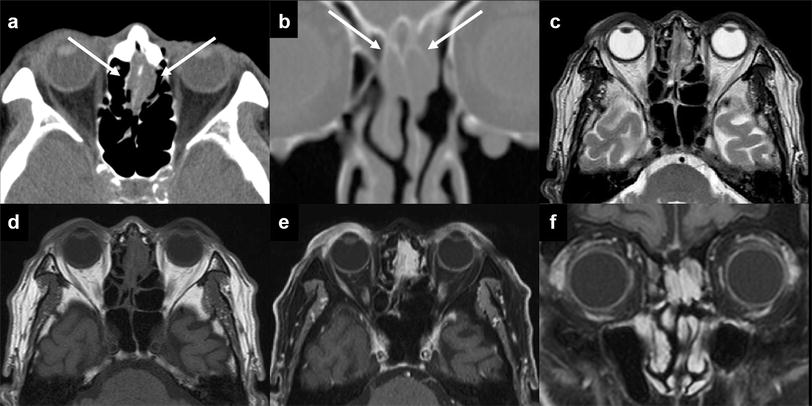

Imaging Features Of Benign Mass Lesions In The Nasal Cavity - Imaging Features Of Benign Mass Lesions In The Nasal Cavity